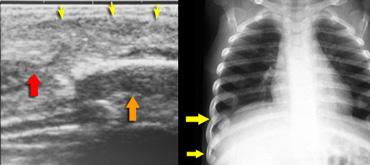

Gãy xương sườn

Trong hành vi lắc mạnh, đứa trẻ bị giữ rất chặt quanh ngực và bị siết chặt trong khi bị lắc.

Điều này nén các xương sườn theo hướng trước-sau và có xu hướng làm gãy chúng ở vị trí gần chỗ bám vào đốt sống và ở phía bên, nơi chúng gần như bị gập đôi.

Do cơ chế chấn thương đặc thù này, gãy xương sườn bên và sau có độ đặc hiệu cao đối với lạm dụng.

Những gãy xương sườn này ở trẻ bị lạm dụng có thể được phát hiện tình cờ trên phim X-quang ngực được chụp vì lý do khác, chẳng hạn như đánh giá viêm phổi.

Gãy xương sườn có độ đặc hiệu cao đối với lạm dụng.

Trong một nghiên cứu tại Hà Lan, tổng cộng 254 gãy xương được tìm thấy trong 56 trường hợp chấn thương đầu do lạm dụng. Tỷ lệ gãy xương sườn và gãy xương hành xương cực kỳ cao (tài liệu tham khảo).

Gãy xương sườn gặp khó khăn tương tự như tổn thương hành xương ở chỗ chúng dễ bị bỏ sót trên phim X-quang.

Trong giai đoạn cấp tính, chúng không rõ ràng trên phim X-quang vì ít có sự di lệch.

Chúng thường được xác định trên phim khảo sát xương toàn thân lặp lại khi các gãy xương đang trong giai đoạn lành, biểu hiện bằng hình ảnh can xương.

Đặc biệt, gãy xương ở đầu bụng của xương sườn là thách thức lớn.

Siêu âm có ích trong việc phát hiện sự di lệch tại khớp sụn-xương sườn phía bụng.

Hình ảnh

Trẻ được đánh giá vì khối mô mềm vùng sụn-xương sườn. Siêu âm cho thấy phù nề mô mềm (mũi tên vàng), phần sụn của xương sườn (mũi tên đỏ) bị tách rời khỏi phần xương (mũi tên cam) của xương sườn. Phim ngực ban đầu âm tính. Phim ngực chụp lại 2 tuần sau cho thấy các gãy xương.